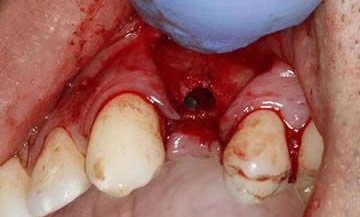

A case of a patient who was a long term resin retained bridge wearer. The resin retained bridge was placed after the patient lost his UL1 many years ago. There was a history of the resin retained bridge lute failing, and due to the loss of the UL1 there was a labio - palatal bone deficit.

A clear acrylic position guide was used to guide implant placement within the aesthetic envelope and guided bone regeneration was used labially to elevate the long standing concavity. A Bonded crown was used to restore the implant and at the 12 month follow up, the bone level around the implant remains unchanged and the patient is confidently smiling.